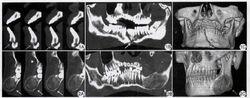

多層螺旋CT對骨骼成像在肌肉骨骼方面的套用

多層螺旋 CT 引入了各向同性成像的概念,它指的是使用原始斷層數據生成具有相同空間解析度的其它方點陣圖像 。 對小範圍掃描而言, 各向同性成像可使用小焦點曝光和超薄切片 (0.5mm), 所得到的多方點陣圖像堪與原 始斷層媲美。

覆蓋更大的解剖範圍

多層螺旋CT對胸部損傷研究許多 CT 檢查需包括胸、腹和盆部內臟器官, 或者成像整個脊柱。用多層 CT 的小準值、 高毫安秒值掃描可獲得大範圍、 高空間和高對比解析度的圖像,而且在多層 CT 軸位數據基礎上, 依據診斷需要可更大範圍地重建冠狀位和矢狀點陣圖像 ,用單層螺旋 CT 是難以勝任的 。